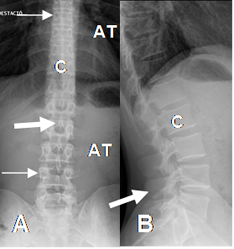

Fig 8. Columna dorsolumbar normal.

A: Rx AP y B: Rx lateral. C: Cuerpo, A: Apófisis transversa, que en el segmento dorsal, se articulan con las costillas. Apófisis espinosa (Flechas gruesas) y pedículos. (Flechas delgadas).